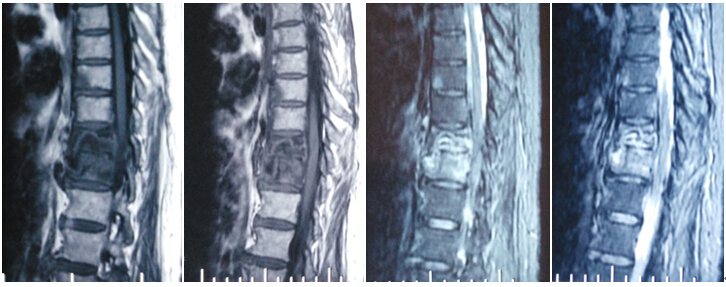

2016年4月29日我科应用椎间孔镜技术、经皮椎弓根螺钉技术成功治疗1例胸椎结核病例。患者女性,67岁,因“胸背部疼痛2月余,加重1月”就诊,经门诊就诊后积极抗结核治疗3周住院治疗。入院患者胸背部疼痛明显,CT示T10、T11椎体骨质破坏,T10塌陷。经科室讨论后应用经皮椎间孔镜技术经椎间孔入路行病灶清除、颗粒骨植骨,再经后路经皮椎弓根螺钉固定。手术顺利,无并发症,目前患者病情平稳。

术前影像学资料